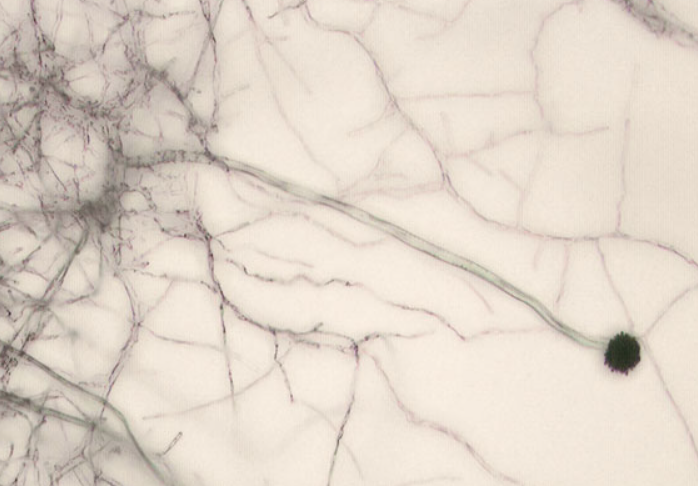

치명적 폐 질환을 일으키는 곰팡이인 ‘아스페르길루스 균류’. 위키피디아

치명적인 폐 질환을 일으켜 매년 250만명의 사망자를 내는 것으로 알려진 곰팡이 ‘아스페르길루스 균류’가 지구 온난화로 분포 지역이 바뀌면서 북미, 유럽, 중국, 러시아 등 고위도 지역에서 더 확산할 수 있다는 주장이 나와 눈길을 끈다.